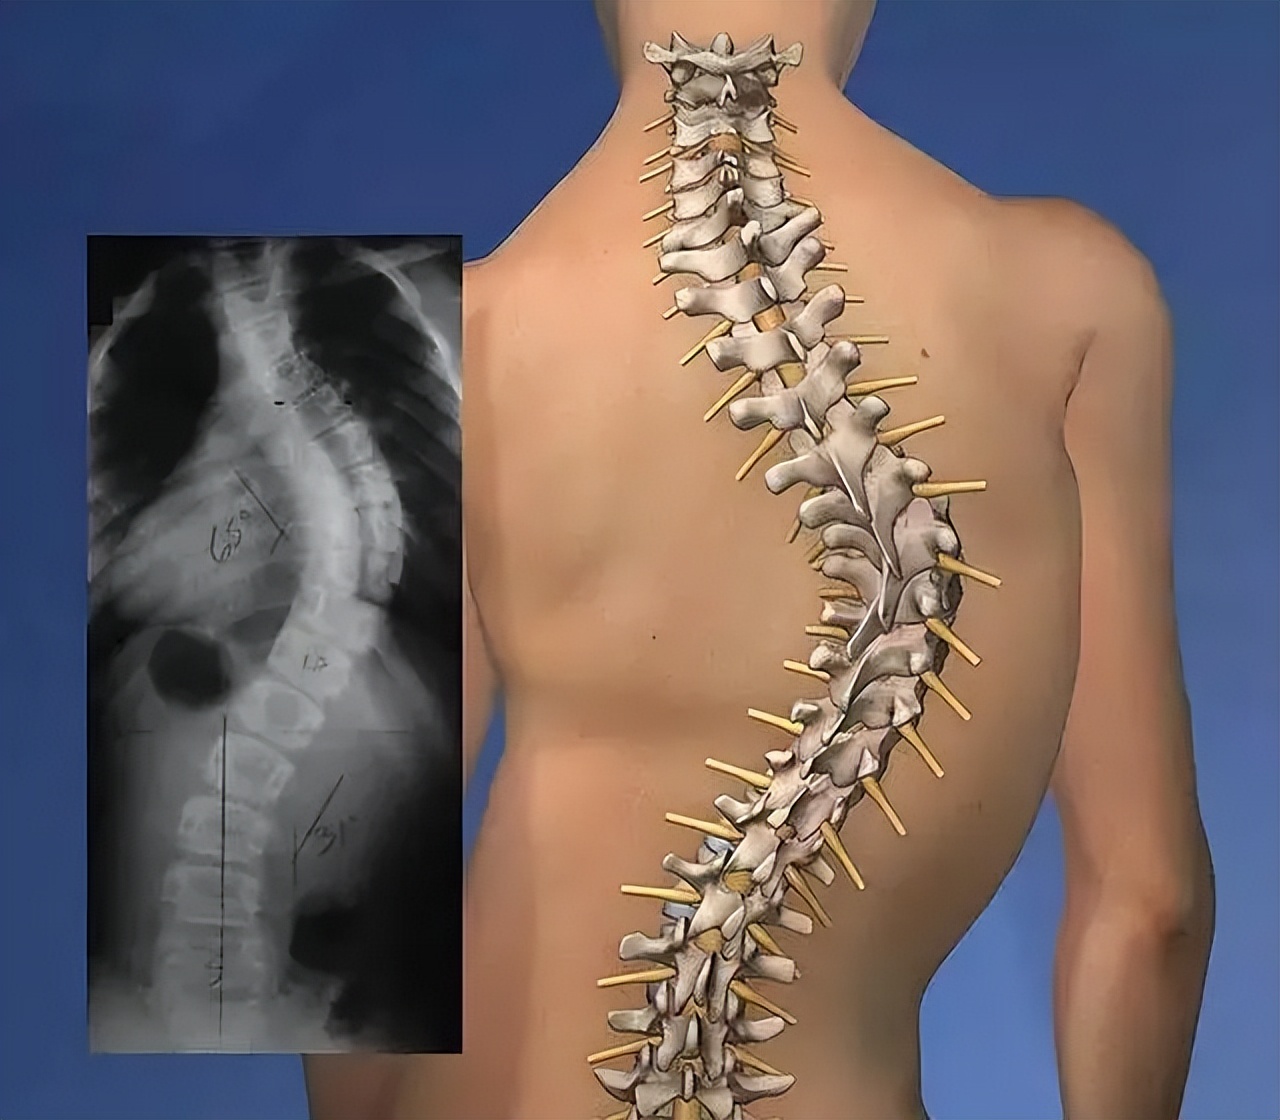

坐姿不良,对于儿童来说,最大的危害就是引起脊柱的侧弯。脊柱侧弯是指脊柱在发育过程中呈现“C”形或“S”形的弯曲,医学上将脊柱弯曲角度≥10度定义为脊柱侧弯(正常的脊柱是直的)。

脊柱侧弯的儿童,脊柱变形

脊柱侧弯严重到一定程度后,无法矫正的情况下,就只能进行手术治疗,脊柱侧弯矫正手术可以说是一种很“恐怖”的治疗方式,花费巨大,因此,脊柱侧弯的预防比治疗要更重要。

好不容易找到一段动画的脊柱侧弯矫正手术动画视频,截了一张图,真实的手术图片太血腥了。手术要在背后拉一道极长的切口,几乎是从颈部到腰部,然后用“螺丝刀”、“钳子”等一顿猛操作。目睹这种手术,真的是后背发凉